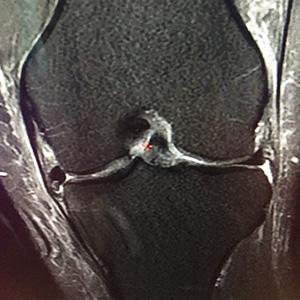

Les ménisques sont des fibrocartilages situés dans l’articulation du genou entre le fémur et le tibia. Ils ont pour but d’amortir les chocs au cours des mouvements du genou, prévenant ainsi les lésions cartilagineuses et le développement de l’arthrose. Il en existe deux par genou, un ménisque interne et un ménisque externe. Ils peuvent se fissurer, spontanément ou après un traumatisme.

A partir de cette fissure, une languette peut venir bloquer l’articulation en flexion (« languette et lésion en anse de seau »). Lorsque la lésion méniscale est douloureuse malgré un traitement rhumatologique bien conduit ou si elle provoque une gêne mécanique considérable (blocage, instabilité...), le traitement chirurgical consiste en l’ablation de la zone lésée lorsque celle-ci n’est pas suturable. C’est la méniscectomie sous arthroscopie. Cette méniscectomie devra être le plus économe possible en ne réséquant que la zone lésée et instable.

Le diagnostic peut être fait par le simple examen clinique, mais une IRM est quasiment toujours réalisée pour confirmer le diagnostic et visualiser la lésion avant de prévoir tout geste chirurgical. Des radiographies seront également toujours réalisées dans le bilan pré-opératoire. Un arthroscanner peut être réalisés à la recherche d’un type lésionnel spécifique ou statuer sur l’état de votre cartilage si l’IRM n’est pas assez contributive. L’intervention n’est pas urgente excepté en cas de blocage de genou.